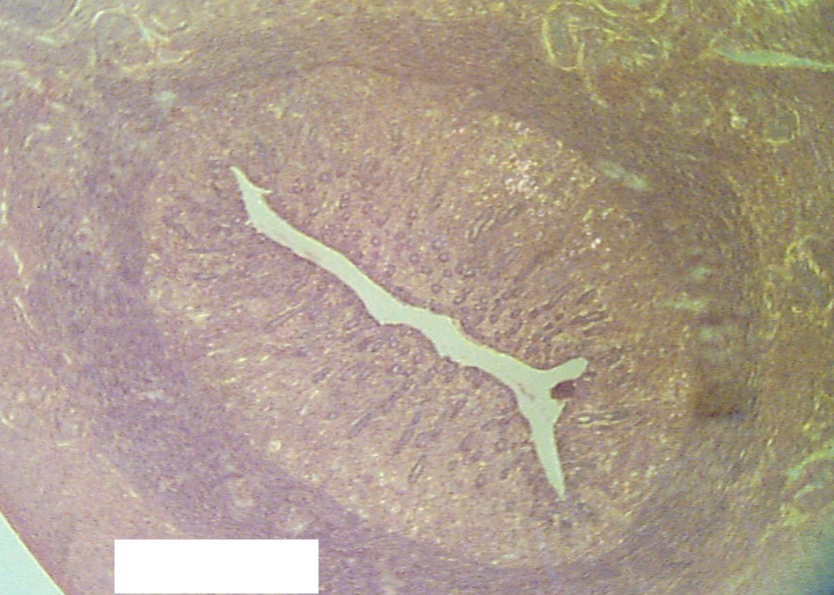

What structure is being depicted in this cross section?

Oviduct